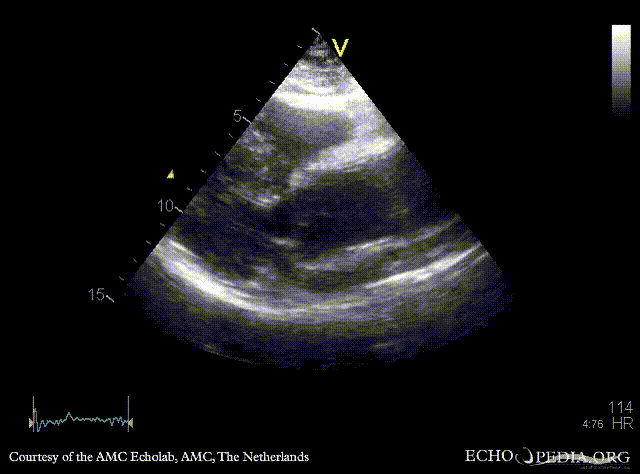

30 Aortic dissection

PLAX: dilated aortic root and ascending aorta PLAX: Color Doppler, mild aortic regurgitation